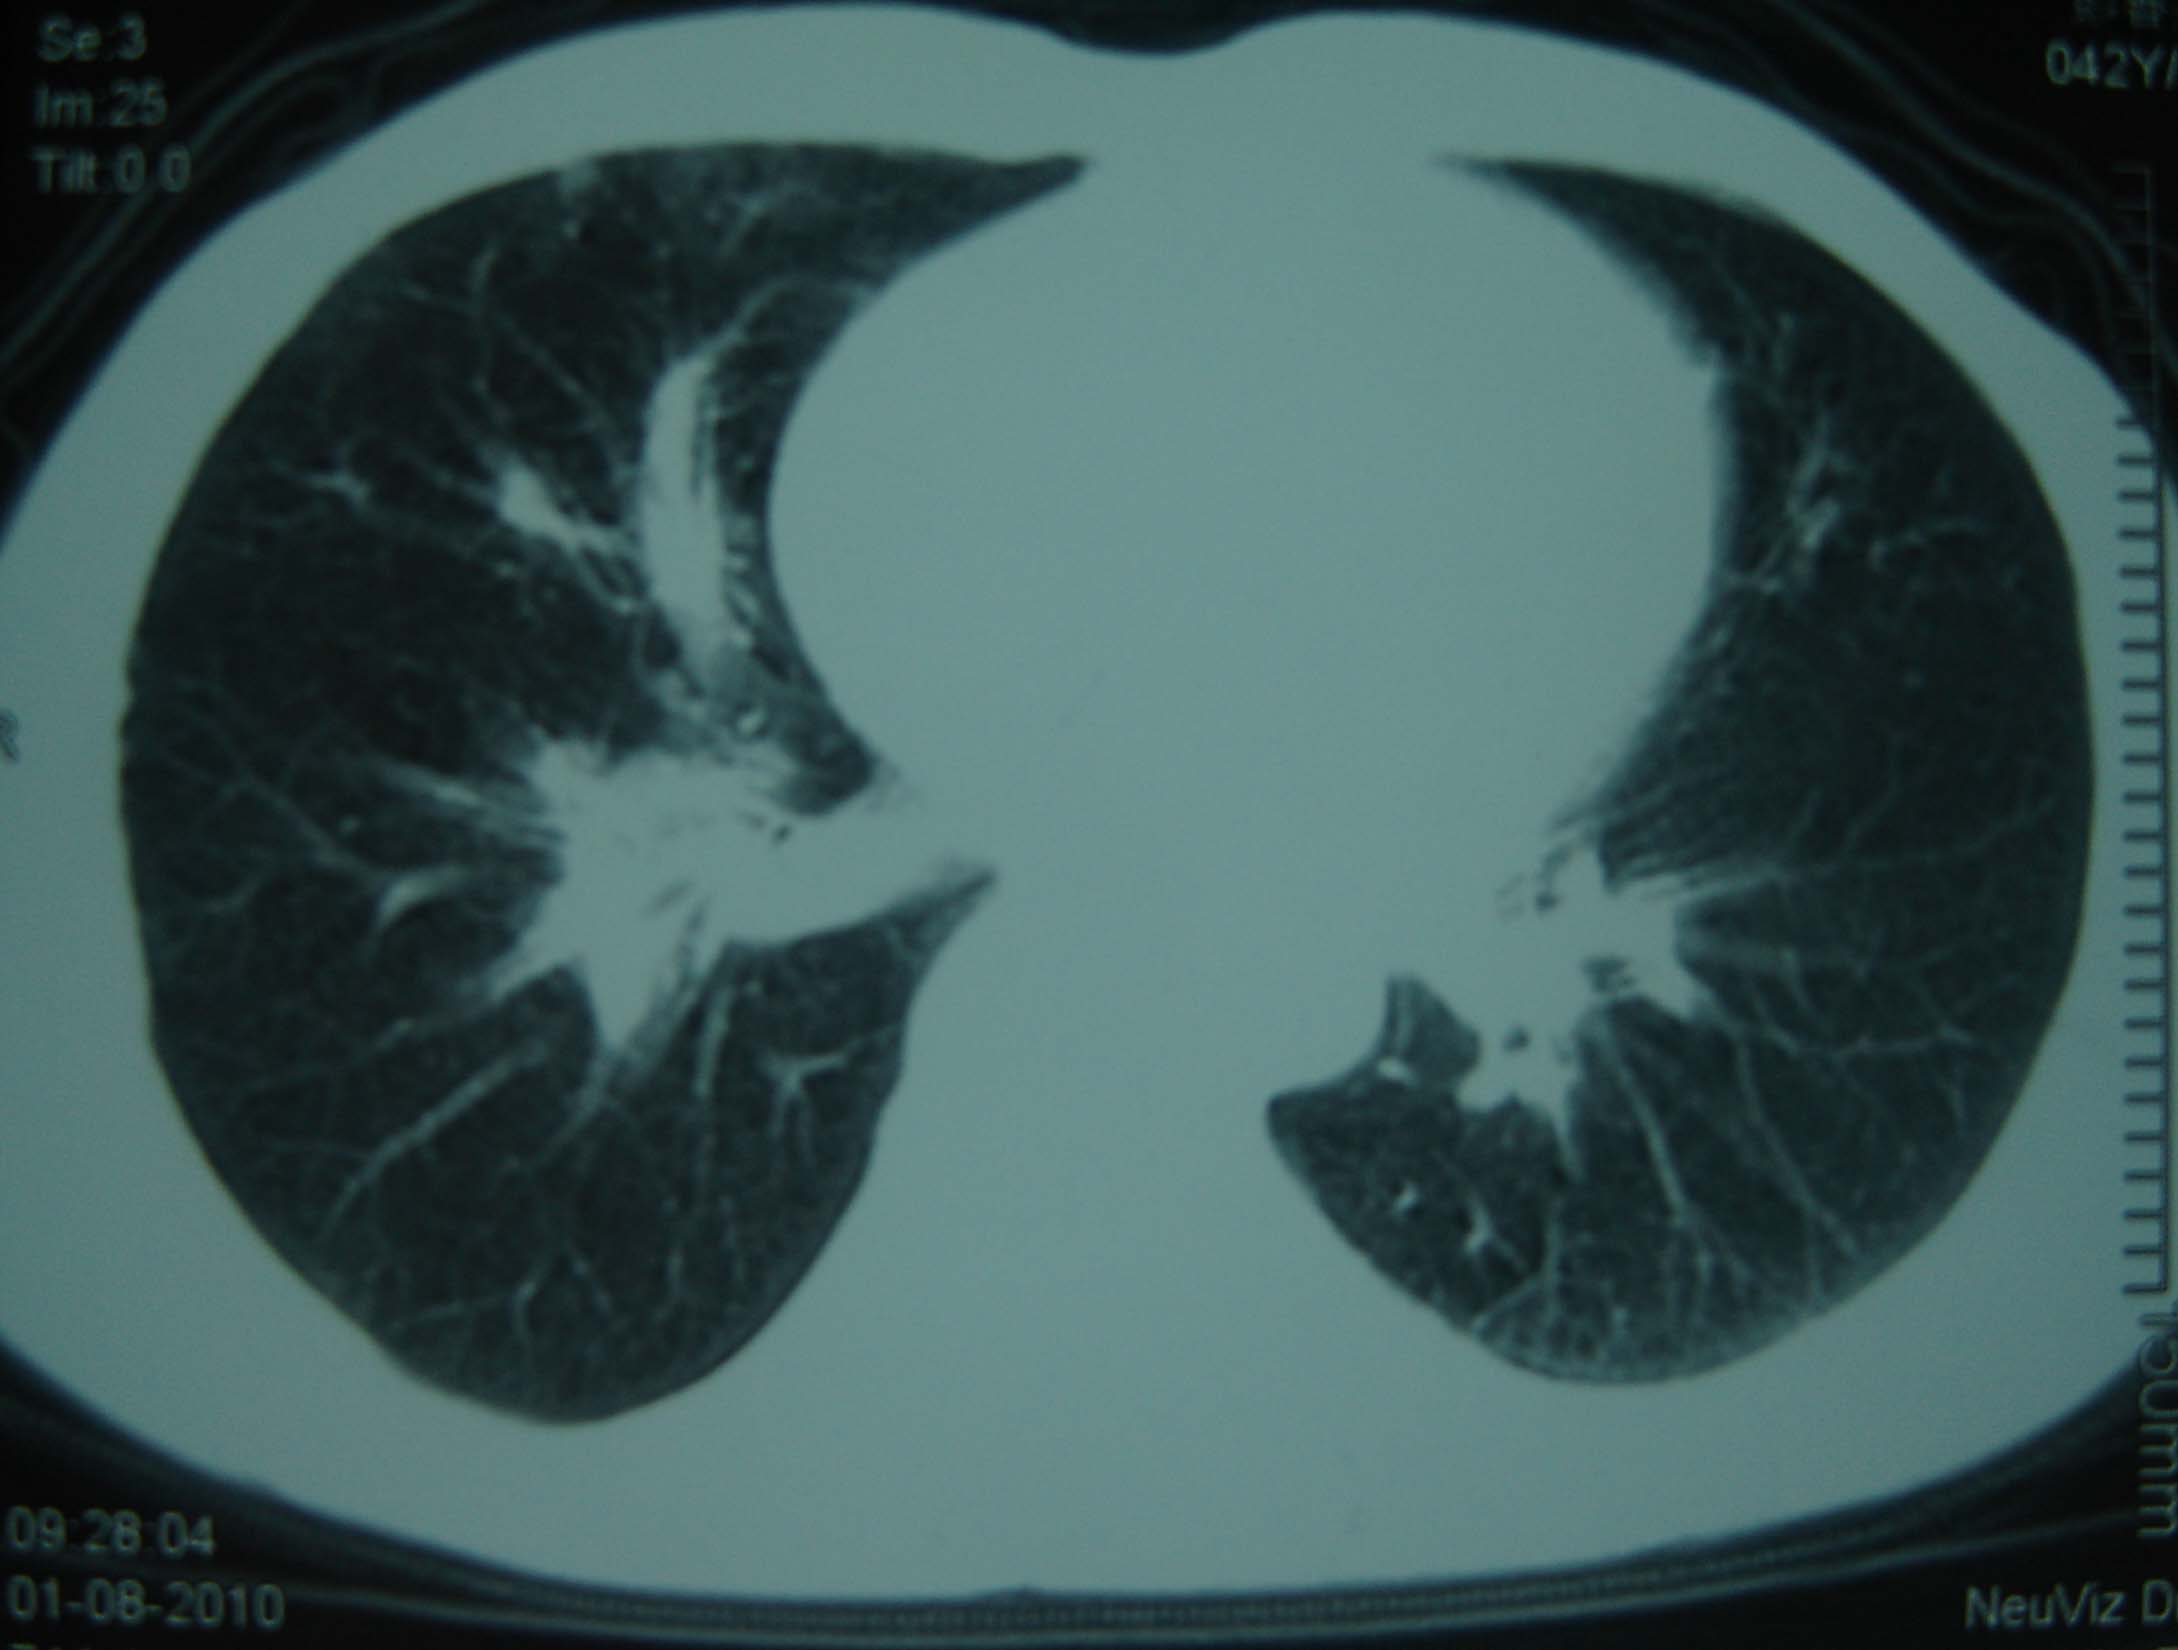

标题: CT25321:两肺多发结节 请会诊 [打印本页]

标题: CT25321:两肺多发结节 请会诊

男 、43岁,咳嗽胸痛,装修工,平时接触粉尘较多,有吸烟史10多年,纤维支气管镜检查未发现异常,胃镜、腹部b超检查亦未发现异常,颈部淋巴结活检未发现肿瘤细胞。

不能排除转移,如果不能找到原发灶,只有短期随访。

结节病?转移瘤?

结节病。

转移瘤?

1)考虑双肺及胸膜多发性转移瘤。2)肺气肿。

双肺结节病。